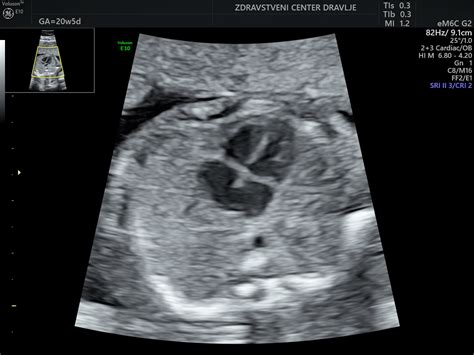

V 19. in 20. tednu se možgani intenzivno razvijajo, intenzivna rast ploda se nadaljuje. Tudi nosečnice, ki so prvič noseče, bodo morda že lahko prvič občutile gibe ploda. V tem času se običajno opravi morfološki ultrazvočni pregled ploda ter določi lego posteljice. V 20. tednu plod meri približno 25 cm v dolžino in tehta približno 300 g. Na koži se pojavi verniks - bela mastna zaščitna snov.